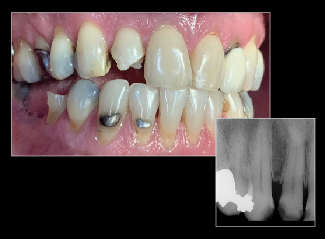

Fig 13. COCO Lux is used here for emergency treatment, blunt force trauma to the right lateral incisor.

Figure 13

Fig 14. Specialist referrals can also be aided by clear photographs. In this case, an image captured using COCO Lux shows the exposure of implant threads and ulcerations under the prosthesis at 2 years.

Figure 14